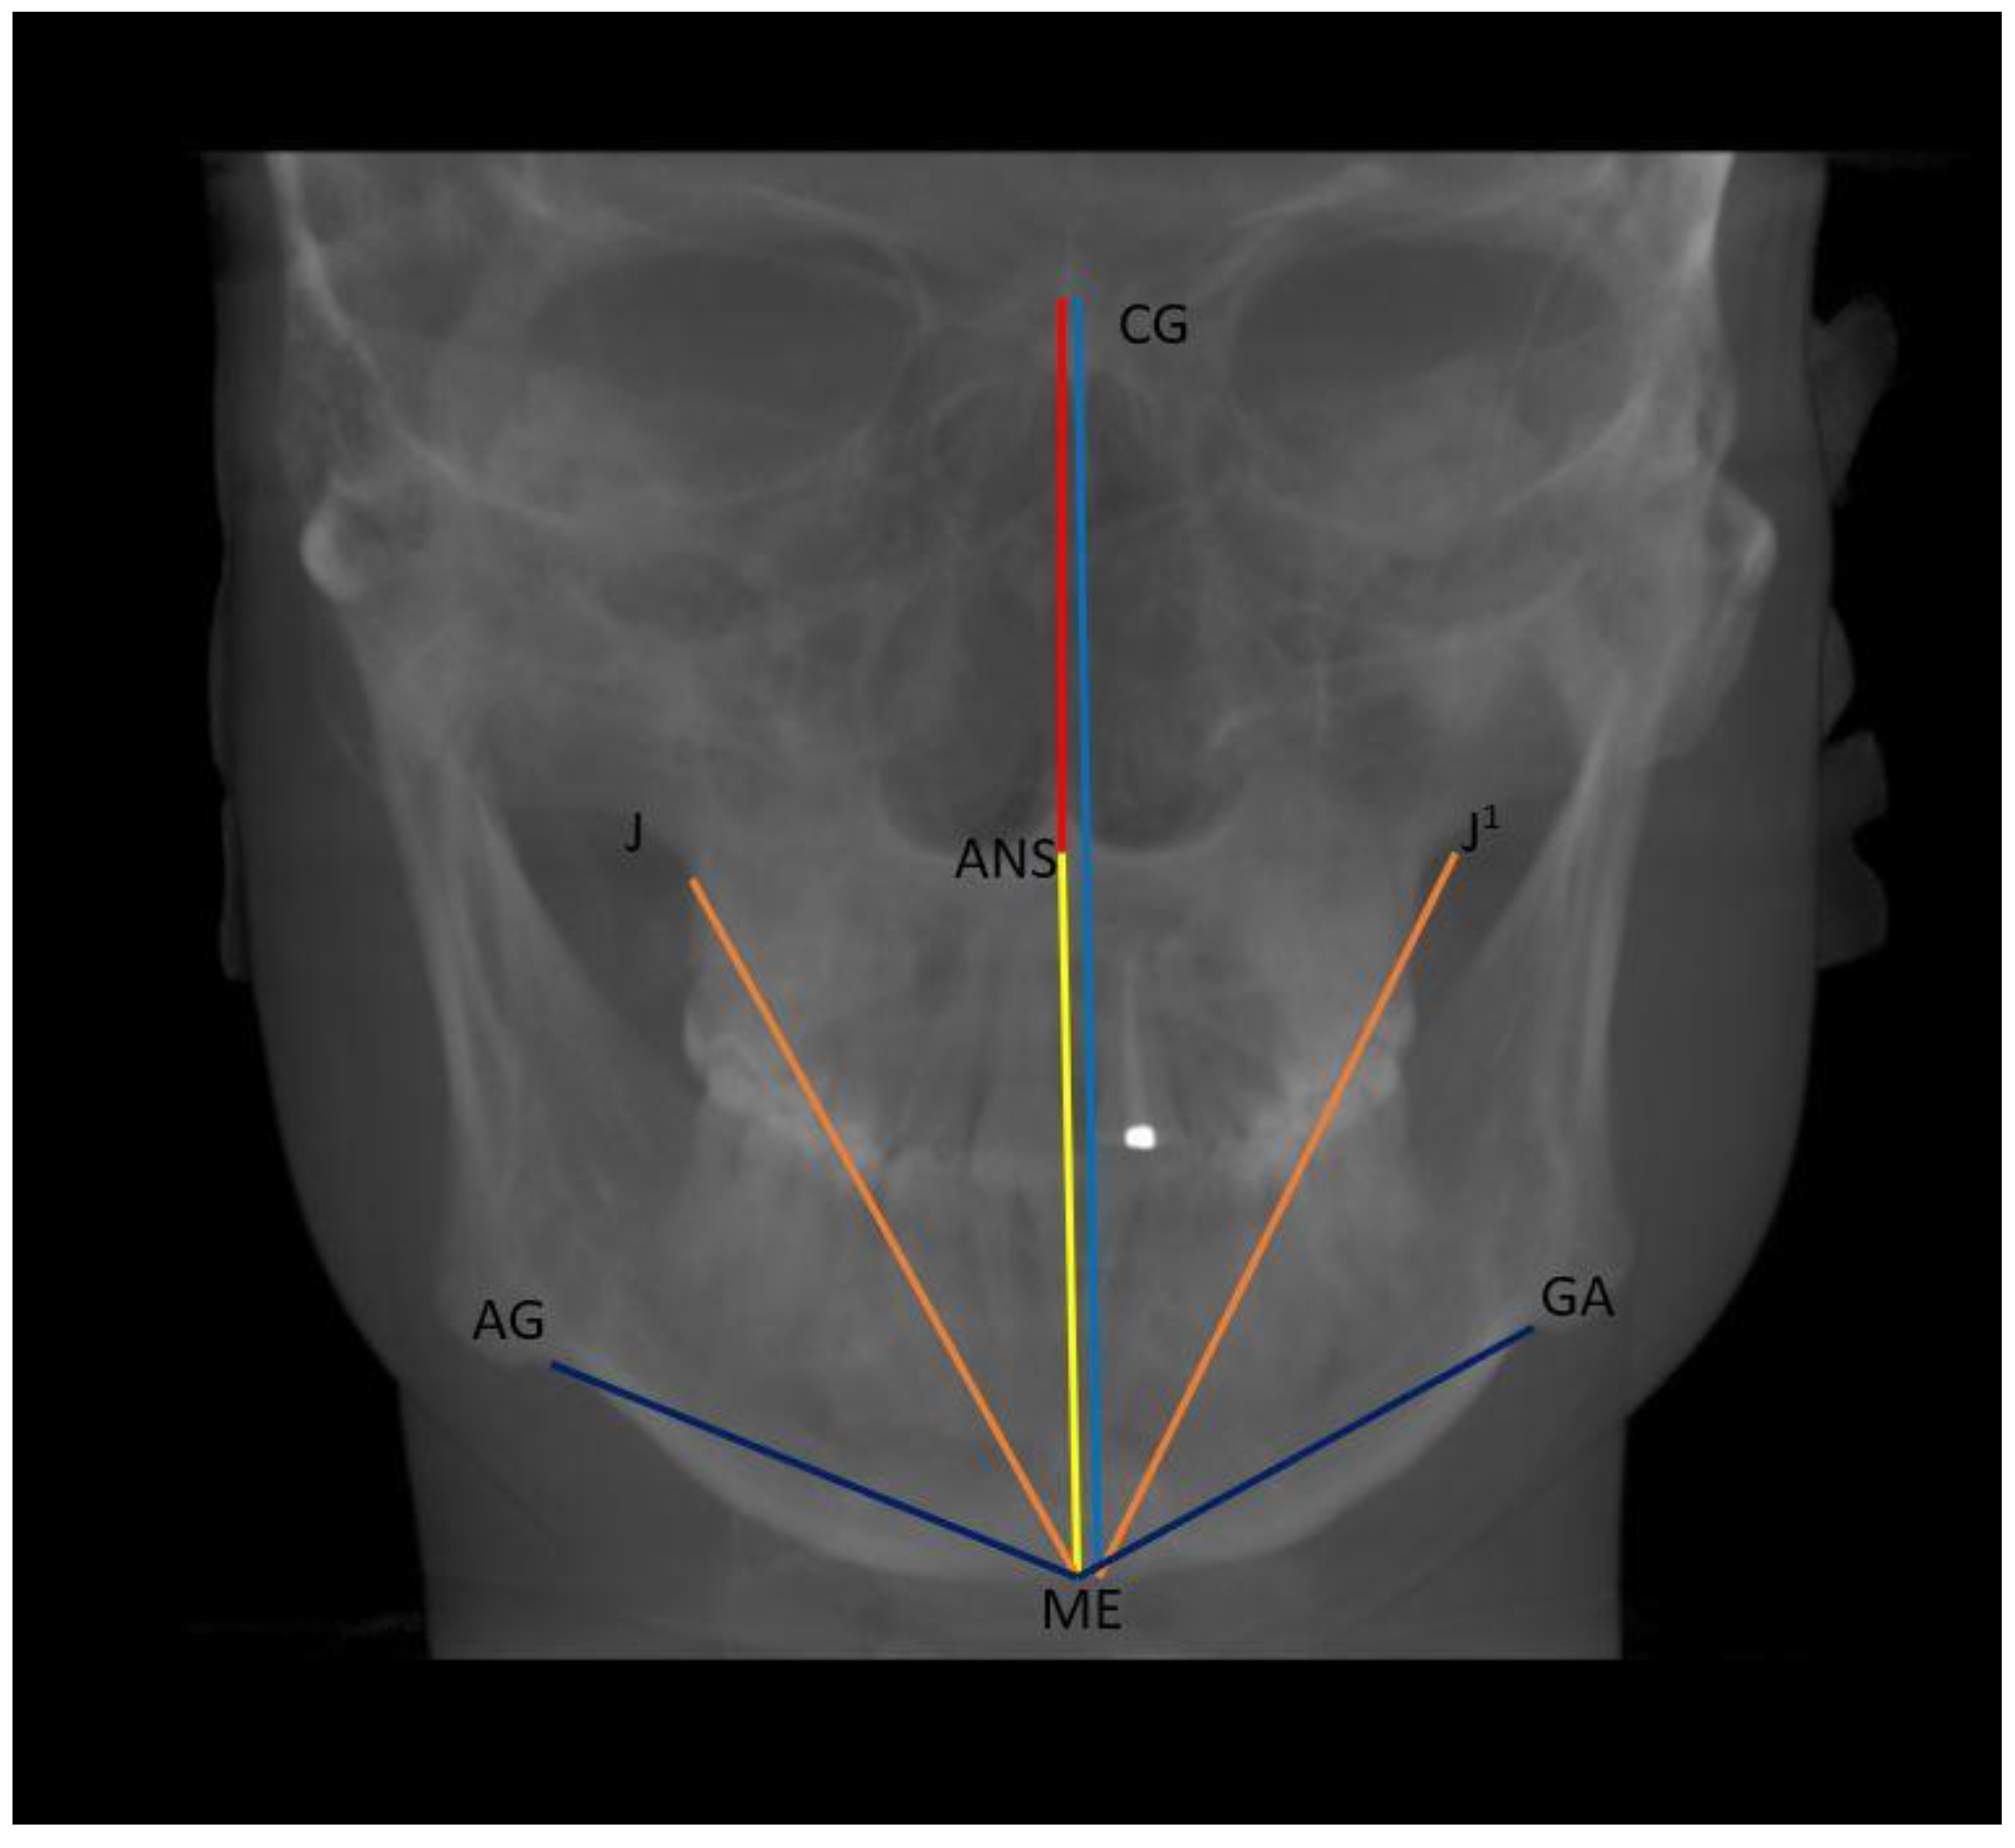

- Vertical: distance between Crista Galli to Menton (Cg–Me), distance between Anterior Nasal Spine and Menton (ANS–Me), distance between Crista Galli and Anterior Nasal Spine (Cg–ANS), distance between Jugal Process and Menton (J–Me left and right), distance between Antegonial notch and Menton (Ag–Me left and right) (Figure 5);